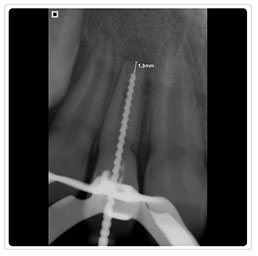

Radiografía Control Endodoncia

Radiografía Intraoral